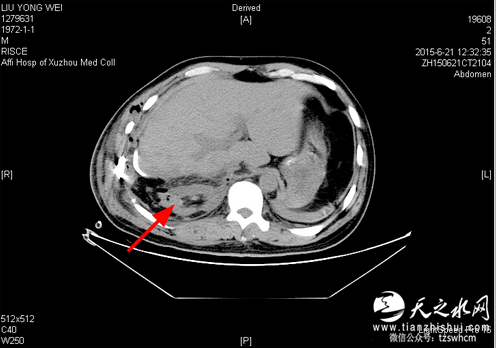

5月5日傍晚,徐医附院针对网络报道发文回应说:“1、近日各大媒体转发了一篇报道“安徽男子术后右肾失踪”。该报道中的内容严重失实。3、患者手术日期:2015年6月20日。3、术后2015年6月21日(术后第1天)和6月25日(术后第5天)的2次CT复查均显示该患者的右肾存在。”并附图一、图二两张CT图片,红色箭头所指方向显示术后第一天和第五天都能看到右肾。

徐州医学院附属医院:2015年6月21日(术后第1天)CT,右肾如箭头所示。